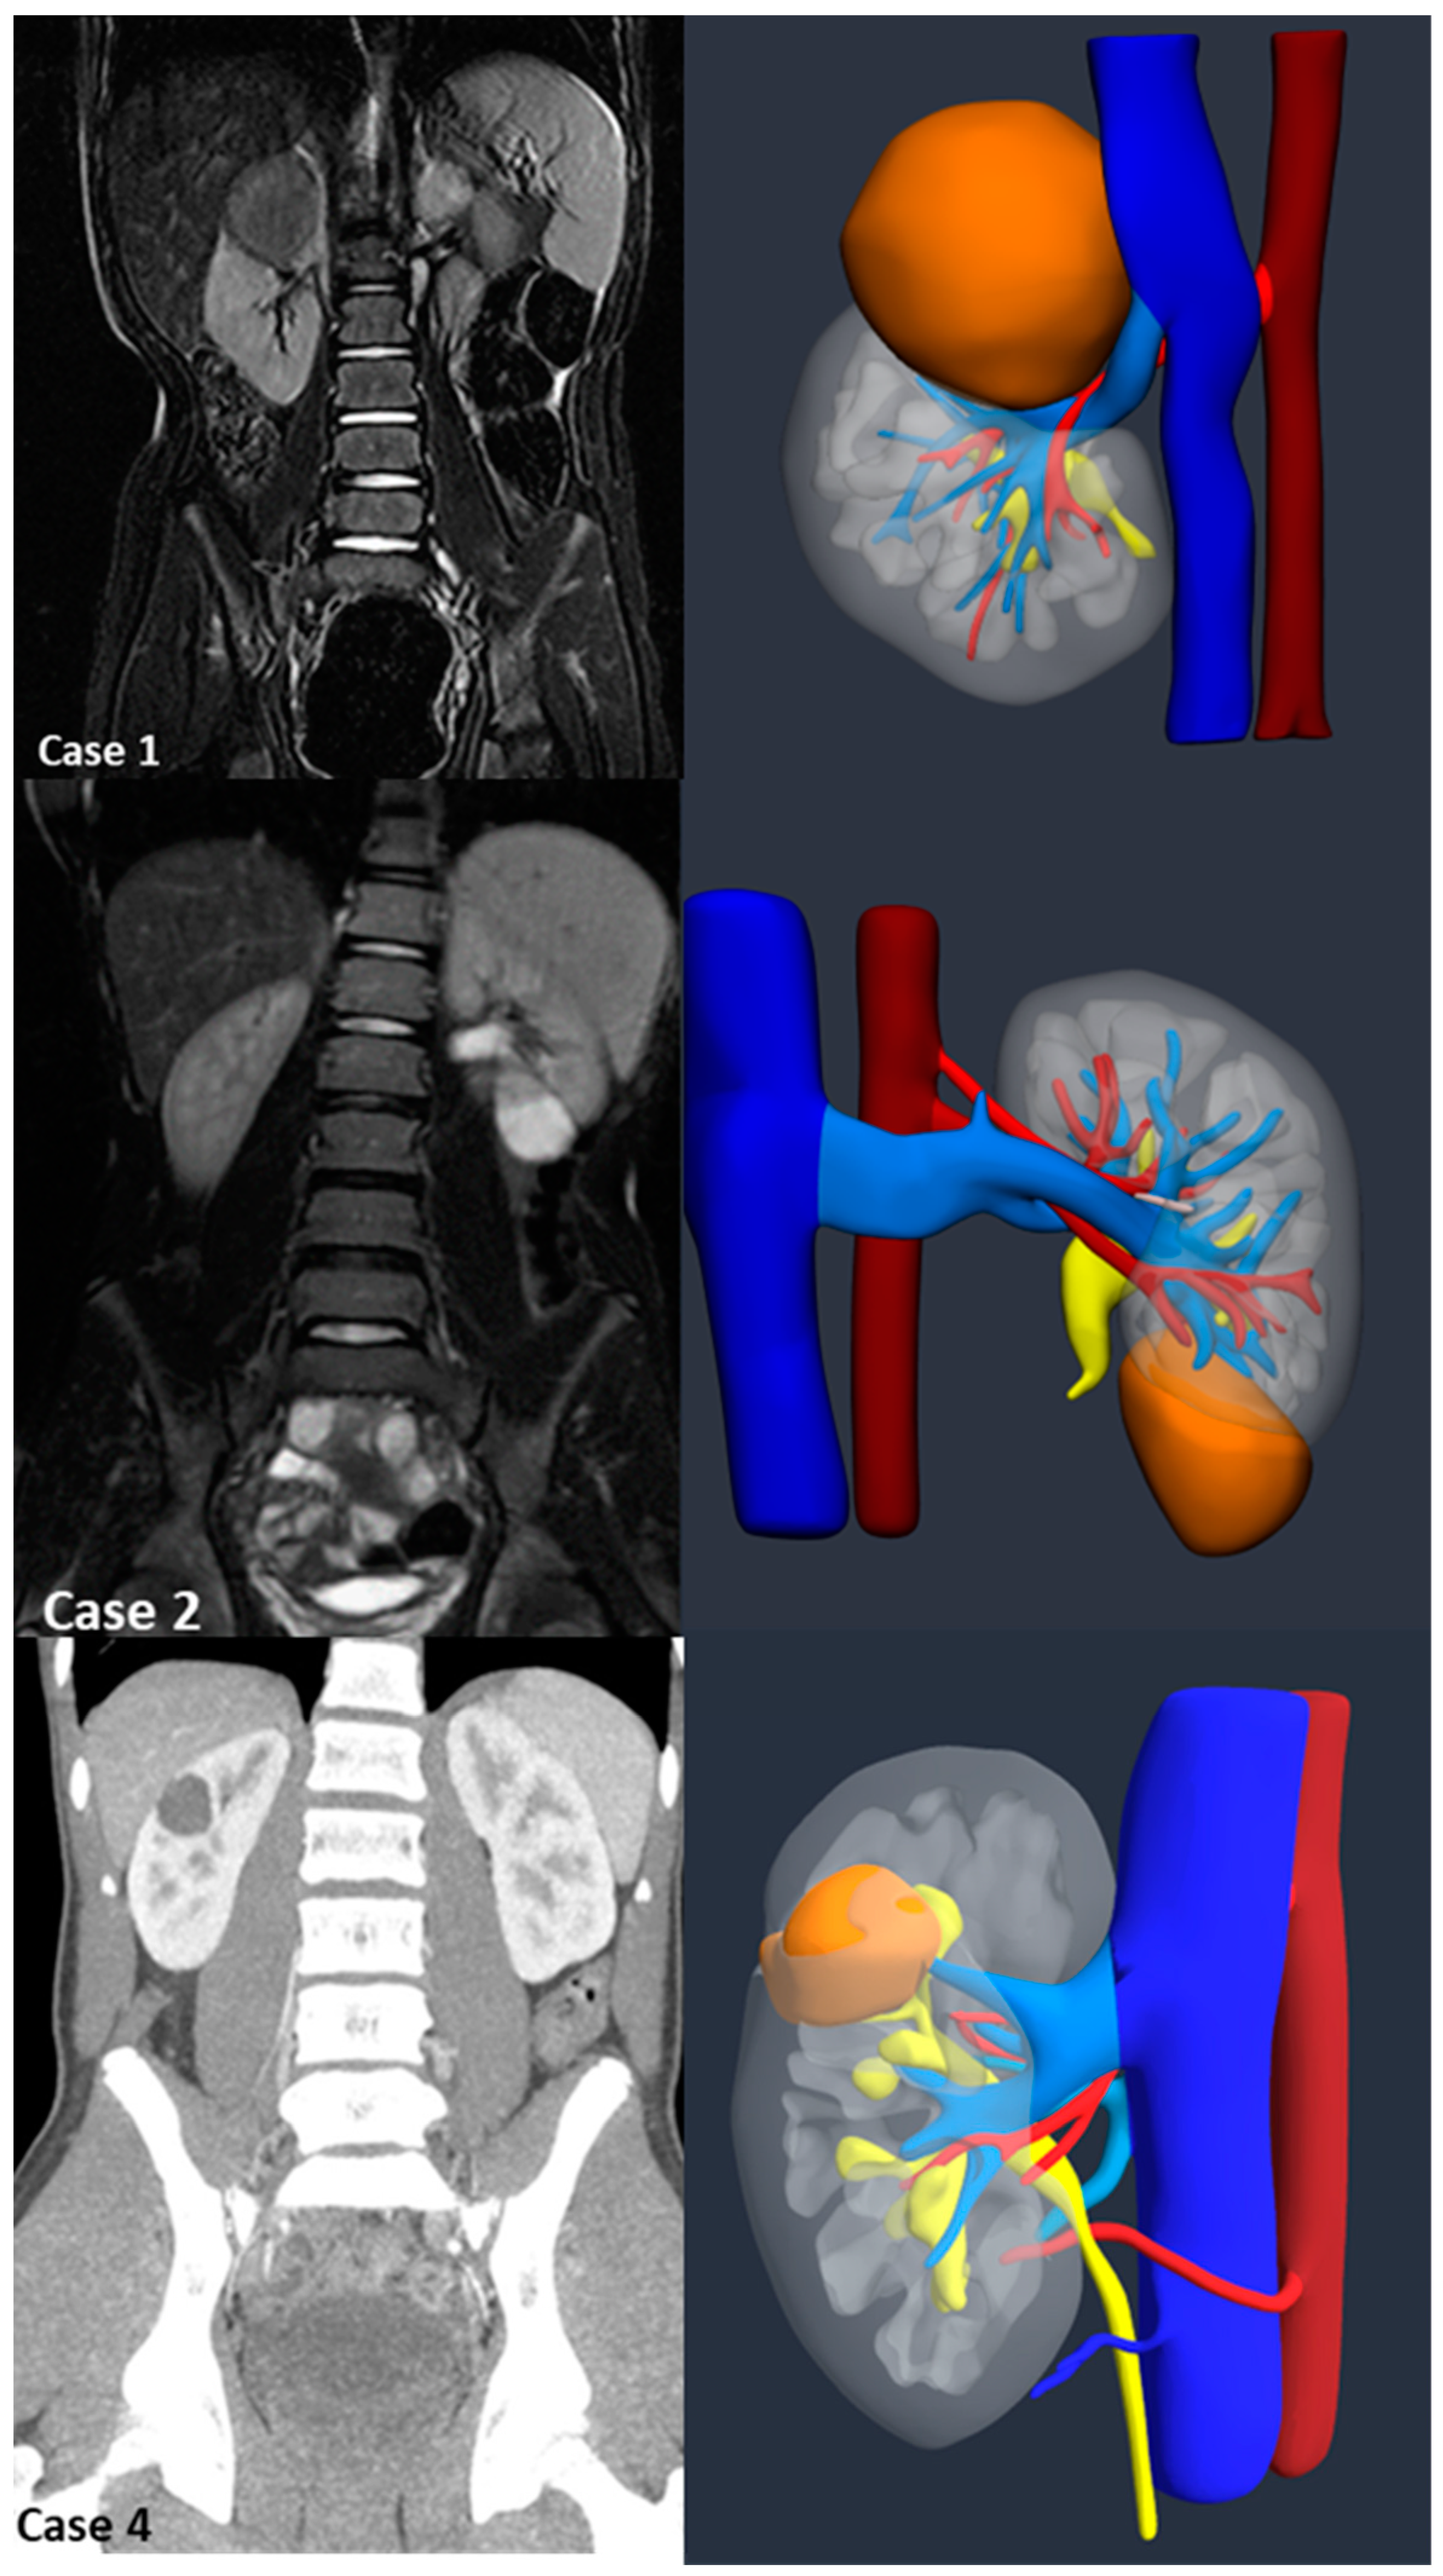

Introduction:The pre-operative planning for complex renal masses in children can be challenging, especially when nephron-sparing surgery (NSS) is recommended. We re-port our experience with the use of 3D-virtual reconstruction (3DVR) and its impact on surgical decision making. Materials and methods: Patients with complex renal masses underwent preoperative 3DVR. DICOM data were obtained from abdominal MRI and/or CT scans. 2D images segmentation was then performed. Three oncology surgeons were asked to individually evaluate each patient's preoperative MRI, CT and 3DVR. A questionnaire regarding the quality of conventional imaging compared to 3DVR was completed following surgery. Results: 8 patients (4♂,4♀) were included: Cases 1,2 and 4 were circumscribed tumours in the right upper pole, left lower pole (Bosniak cyst IV) and right mid-upper pole (Bosniak cyst IIF) respectively; Case 3 was a large hilar mass involving the whole kidney, unresponsive to chemotherapy; Case 5 and 7 were stage IV Wilms' tumour with venous thrombosis; case 6 was a left mid lower renal mass in a patient with WAGR syndrome and acute lymphoblastic leukae-mia (ALL) and case 8 was a recurrent central right WT after previous NSS in a child with Beckwith-Wiedemann syndrome(BWS). Four radical nephrectomies and three NSS were performed. In comparison to conventional imaging, the 3DVR models were judged to be superior by the expert reviewers for all anatomical structures except the urinary tract(p< 0.05). Conclusions: Our study suggests that 3DVR can be considered a useful tool in the pre-operative evaluation of children with complex renal masses and can facilitate NSS in selected patients.

| Case | 1 | 2 | 3 | 4 | 5 | 6 | 7 | 8 |

| Sex (M/F) | F | M | M | M | F | F | M | F |

| Age (months) | 48 | 180 | 14 | 178 | 50 | 42 | 28 | 52 |

| Weight (kg) | 15 | 50 | 9.4 | 70 | 18 | 10.8 | 13 | 17 |

| Side | Right | Left | Left | Right | Right | Left | Left | Right |

| Position | UP | LP | UP+MP+LP | MP+UP | UP | MP+LP | LP | LP |

| Volume (ml) at surgery | 33 | 24 | 597 | 23 | 421 | 63 | 136 | - |

| Syndrome | - | - | - | - | - | WAGR | - | BWS |

| MRI | X | X | X | X | X | X | X | X |

| CT scan | X | X | - | X | X | X | X | X |

| Vein Thrombosis | - | - | - | - | X | - | X | - |

| UCSI | - | - | - | - | - | X | - | - |

| Surgery | RAL NSS | RAL NSS |

Open nephrectomy | RAL NSS | Open Nephrectomy | Open Nephrectomy | Open Nephrectomy | - |

| Operative time (minutes) | 210 | 200 | 240 | 150 | 450 | 310 | 320 | - |

| Histology | WT | TRCC | CN | CN | WT | WT | WT | - |